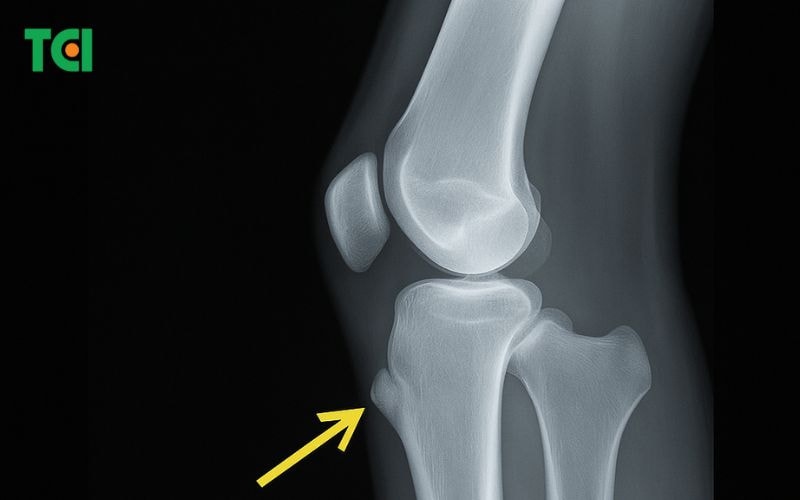

4.2. Chẩn đoán hình ảnh

Trong trường hợp cần thiết, bác sĩ có thể chỉ định X-quang để loại trừ các bệnh lý khác ở gối như gãy xương, u xương hay tổn thương sụn. Hình ảnh thường cho thấy sự dày lên của lồi củ chày hoặc các điểm viêm quanh gân bánh chè.